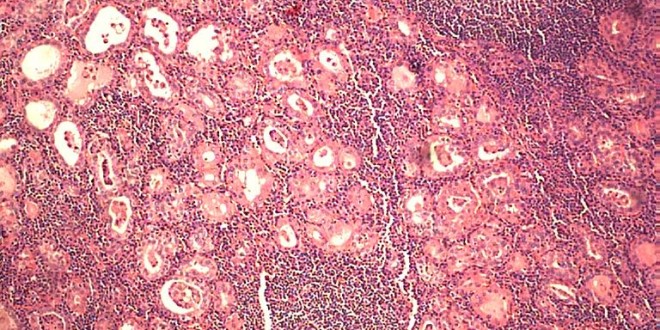

Microscópicamente existe una importante pérdida neuronal difusa, cambios espongiformes (con forma que recuerda a la esponja) y astrocitosis (proliferación de astrocitos, un tipo de células del sistema nervioso), que puede afectar todas las regiones, pero sobre todo a la región denominada calcarina.

El hígado presenta una marcada atrofia con fibrosis (proliferación del tejido conectivo fibroso), esteatosis (infiltración grasa del tejido), inflamación, proliferación de los conductos biliares y a menudo cirrosis (fibrosis, proliferación del tejido conectivo fibroso, hepática). Insistimos de nuevo que es de suma importancia el uso de la Trofología, para detener en lo máximo de lo posible estos efectos negativos para la salud del paciente.

Los cambios histológicos hepáticos incluyen esteatosis micro vesicular, proliferación de los conductos biliares, inflamación focal, fibrosis periportal y necrosis celular.

El SNC se constata una grave pérdida neuronal, cambios espongiformes y proliferación astrocitaria.